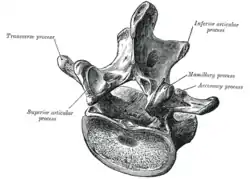

![]() Будова поперекового хребця | |

Від тіла хребця назад йде дуга, яка замикає хребетний отвір і переходить далі до остистого відростка. У площині дуги в обидві сторони розташовані поперечні відростки, які є рудиментами ребер. Біля основи поперечних відростків поперекових хребців видно рудимент справжніх поперечних відростків (processus accessorius), який при великій довжині (4 мм) набуває форму шила — шилоподібний відросток (processus styloideus). Автори М. Г. Привєс, М. К. Лисенков, В. І. Бушкович зауважують, що його не слід приймати, як патологічне утворення. На верхній і нижній гранях дуги розташовані парні верхні і нижні суглобові відростки. У чотирьох верхніх поперекових хребцях остисті відростки спрямовані прямо назад, суглобові розташовані сагітально. Хребетні отвори, починаючи з другого поперекового хребця, поступово звужуються, що пов'язано з анатомією спинного мозку.

Тіло п'ятого поперекового хребця в напрямку до остистого відростка має клиноподібну форму, при цьому воно нахилене вперед, бо крижова кістка спрямована назад, формуючи кіфоз. Суглобові відростки розміщені в напівфронтальній, напівсагітальній площинах.